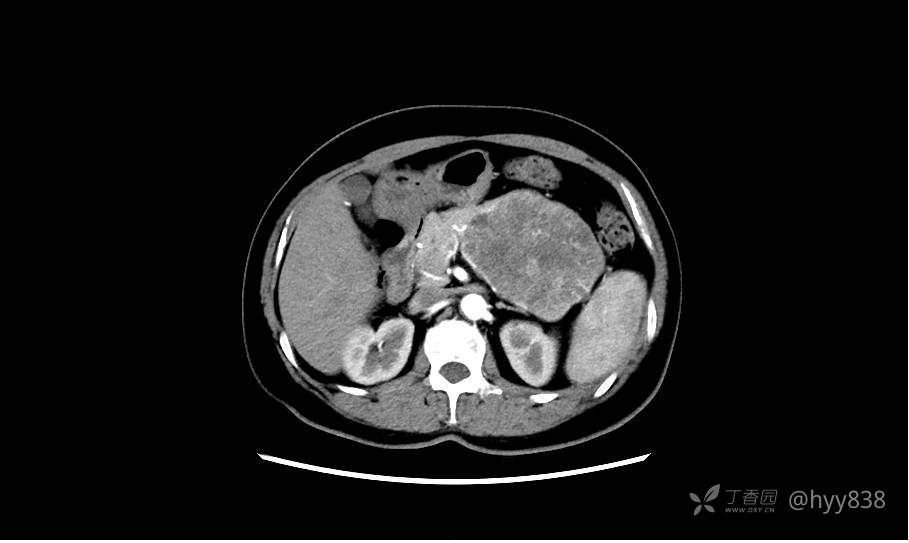

静脉期(机器故障---延迟期了)